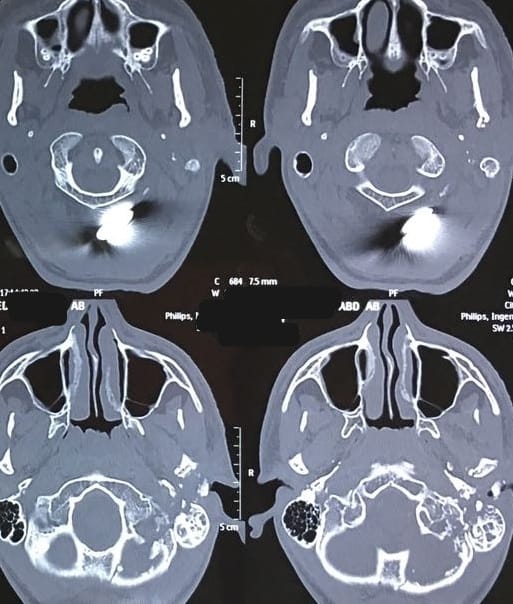

كان المستشفى الرئيسي قد استقبل شاب يبلغ من العمر ١٦ عاما، في حالة غيبوبة، نتيجة استقرار رصاصة خلف أذنه اليسرى، مما تسبب في قطع تام بالعصب الوجهي السابع، وبعد قضاء أسبوعين في العناية المركزة، خضع المريض لعملية جراحية دقيقة لاستكشاف العصب السابع، حيث قام الأستاذ الدكتور محمد محمود رشدي، بتحديد مكان القطع في العصب، ونظرا لتلف جزء كبير من العصب، قام الأستاذ الدكتور محمد مدثر أبو شنيف، بإجراء عملية جراحية استغرقت ٦ ساعات، لأخذ وصلة عصبية من أحد الأعصاب الحسية الجلدية وإعادة توصيل العصب السابع بالعصب المسئول عن حركة اللسان، دون أي تأثير على حركة اللسان.

لتستقر حالة المريض، حيث أظهرت المتابعة المستمرة تحسنا ملحوظا في عضلات الوجه، وعادت حركة الوجه إلى طبيعتها بشكل كامل، ليعود الشاب لممارسة حياته بشكل طبيعي بعد أكثر من عام من المتابعة الدقيقة.